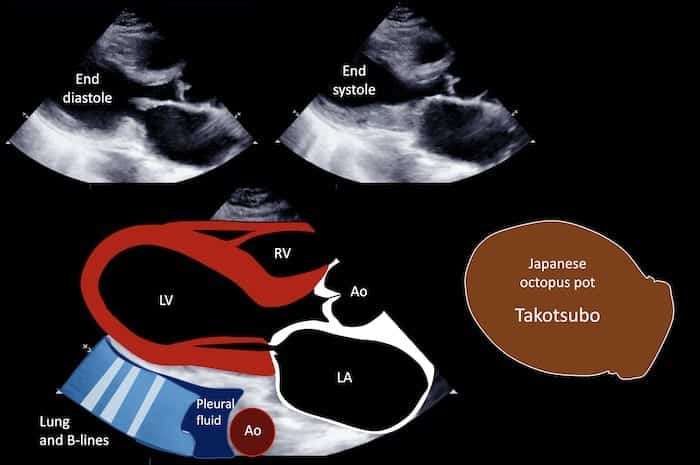

Originally described in Japan in 1990, the condition is named after the takotsubo pot, a traditional basket used in Japan to catch octopi. In TCM, apical dyskinesia and subsequent ballooning creates an LV appearance remarkably similiar to this octopus pot.

- Transient dyskinesis of the LV apical and/or midsegments

- Regional wall motional abnormalities beyond a single epicardial vascular distribution